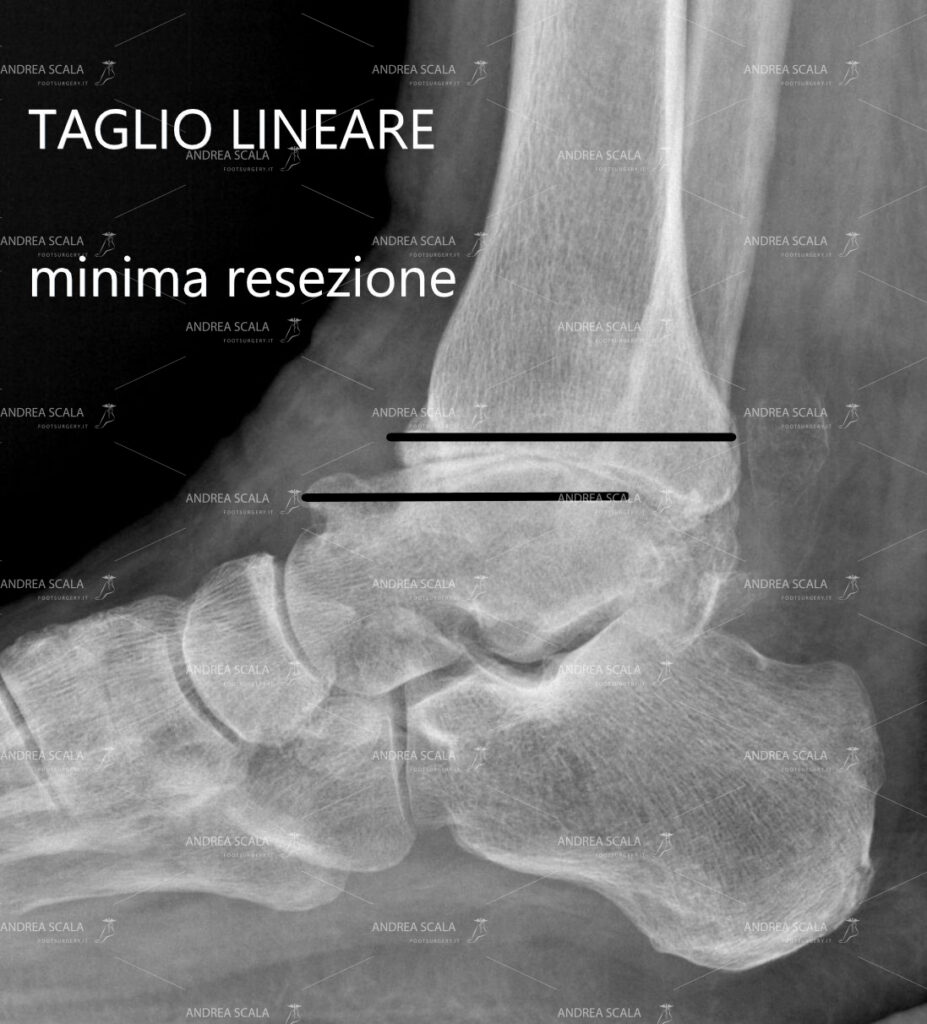

L’appiattimento della tibia e lo schiacciamento dell’astragalo e è la situazione in cui si trova più frequentemente il paziente. Le protesi che fanno un taglio lineare sembra che rispettino maggiormente la situazione delle superfici ossee appiattite e risparmiano più osso.

Soprattutto quando si deve tagliare la superficie appiattita della tibia e dell’astragalo è pressoché inutile operare una resezione curva. Il taglio lineare è quello che rispetta di più la patologia della artrosi. La quantità di osso asportata con il taglio tangenziale è minimo.

La figura mostra il confronto tra la caviglia normale e la caviglia artrosica. Nella normalità c’è una naturale curvatura della tibia e dell’astragalo. Nella artrosi la tibia e l’astragalo presentano superfici appiattite.

Nei casi di appiattimento delle superfici articolari quando si cerca di realizzare la resezione curva si corre il rischio di asportare più osso del dovuto e di invadere l’articolazione sottostante alla caviglia

Nei casi di appiattimento delle superfici articolari la resezione lineare consente di asportare una minima quantità di osso del paziente